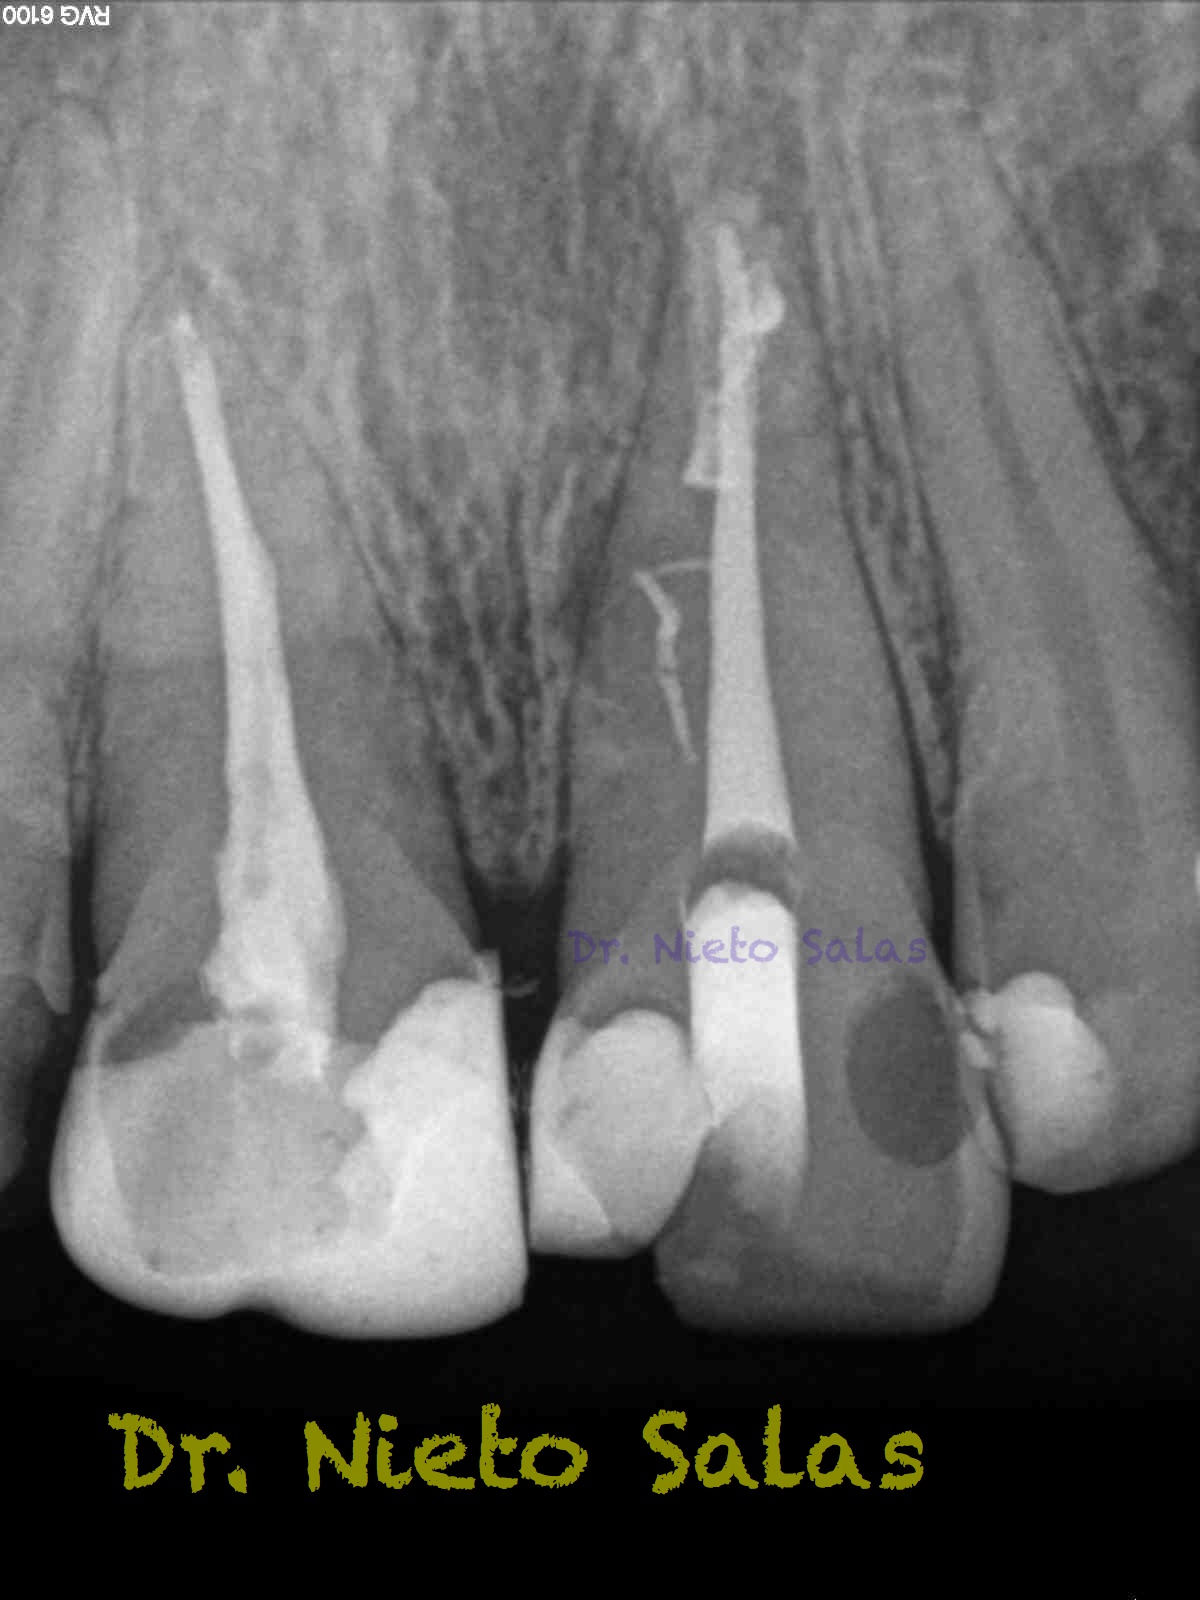

Pero no todo se va a dejar al «poder de la irrigación»,  es muy importante la biomecánica, y la intuición para poder instrumentar esos pequeños conductos laterales que es muchas ocasiones nos dan problemas. Así, pues, os pongo un par de casos que con ayuda de esta «intuición» pudimos hacer un buen tratamiento.

Presentaban un sondaje normal, y sospechamos de que podía tratarse de lesiones por conductos laterales.

Una vez que hemos desbridado biomecánicamente con limas de muy pequeño diámetro, obturamos:

Y este sería el otro caso:

Es muy importante cambiar la proyección de las Rx para tener más información de como hemos sellado el sistema de conductos.